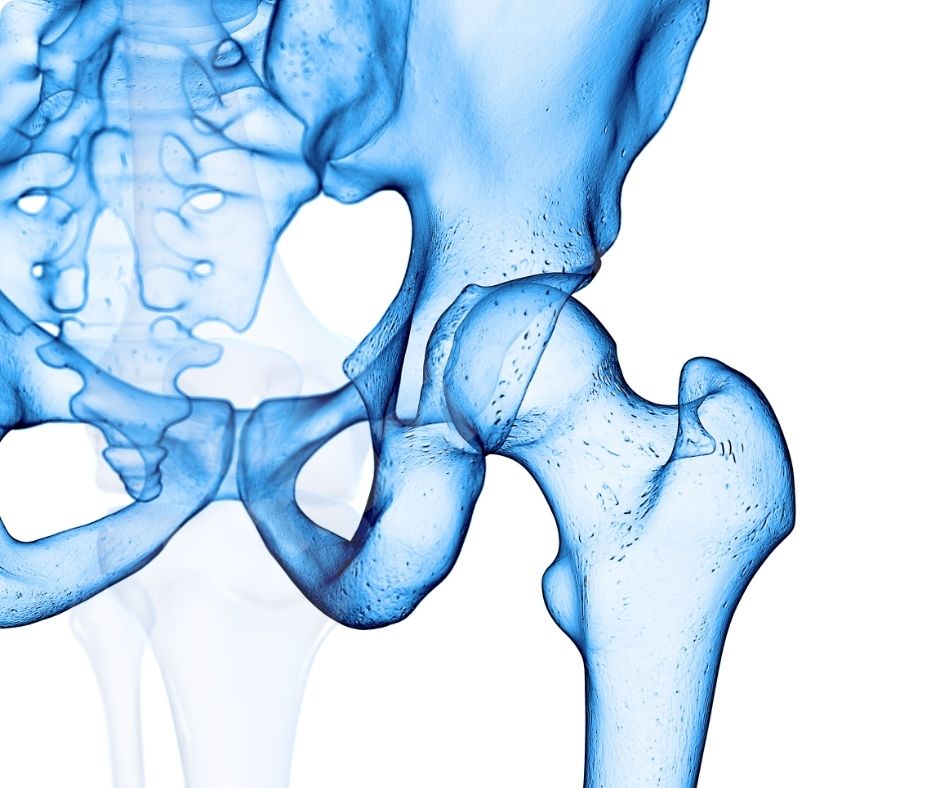

글루코사민은 신체 내에서 자연적으로 생성되며, 연골의 주요 구성 요소로 관절의 유연성과 기능을 유지하는 데 중요한 역할을 합니다. 특히 관절염과 같은 관절 문제를 예방하거나 완화하는 데 유용한 보충제로 많이 사용됩니다.

연골 보호 및 재생

글루코사민은 연골 조직의 구성 요소로서 연골의 손상을 막고 재생을 촉진합니다. 이는 특히 고령자나 관절에 많은 부담이 가는 운동을 하는 사람들에게 중요합니다. 글루코사민의 연골 보호 효과는 관절염의 진행을 늦추고 삶의 질을 향상시키는 데 큰 도움을 줍니다.